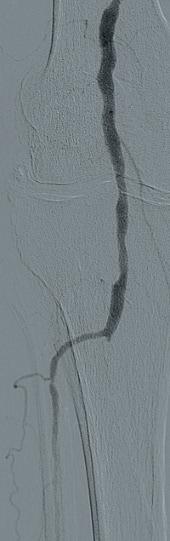

Subsequent diagnostic angiography confirmed the high grade left CFA stenosis (Figure 1) and the long SFA occlusion with diminished contrast flow below the knee. The deep femoral artery showed no significant stenosis within the first centimetres. For

In this case example, a 79-year-old man with severe claudication of the left leg was admitted to our angiology department. Cardiac risk factors included poorly controlled diabetes, renal insufficiency (GFR 27ml/min), severe obesity (body mass index [BMI] 38) and hyperlipoproteinaemia. On duplex ultrasound, a severe calcified short 90% CFA stenosis and a long 30cm occlusion of the superficial femoral artery (SFA) from the origin to popliteal artery (PA) segment one was diagnosed. The posterior tibial artery

DCB PTA catheter, BD Bard) which was inflated for three minutes at 8atm. Subsequent angiography showed a very good lumen gain without significant restenosis within the target lesion (Figures 3 and 4). We finalized the intervention with full recanalisation of the SFA using three more DCBs and one bailout stent implantation using the new triaxial, 4F Pulsar-18 T3 nitinol self-expanding stent system (6x150mm; Biotronik). After implantation of the Pulsar-18 T3 stent and a 6mm balloon post dilatation, a brisk flow was seen within the whole length of the target vessel and a straight flow into the foot via the patent posterior tibial artery. Follow-up examination of the patient the next day showed an ABI of 0.9 on the left side.

recanalization, a crossover approach from the right groin was performed using an 8F crossover Destination reinforced introducer sheath (Terumo). Using an 0.014” Glidewire Advantage guidewire we were easily able to pass the high-grade CFA stenosis with the guidewire.

A 7x60mm IVL catheter was delivered across the lesion and the integrated balloon was expanded to 4atm to facilitate efficient energy transfer. After four calcium modification cycles, we used the integrated balloon to dilate the lesion at 6atm pressure in order to maximize luminal gain. The IVL catheter was then exchanged to an 8x40mm drug-coated balloon (DCB; Lutonix 035

Figure 1

Figure 2

Figure 3

Figure 4